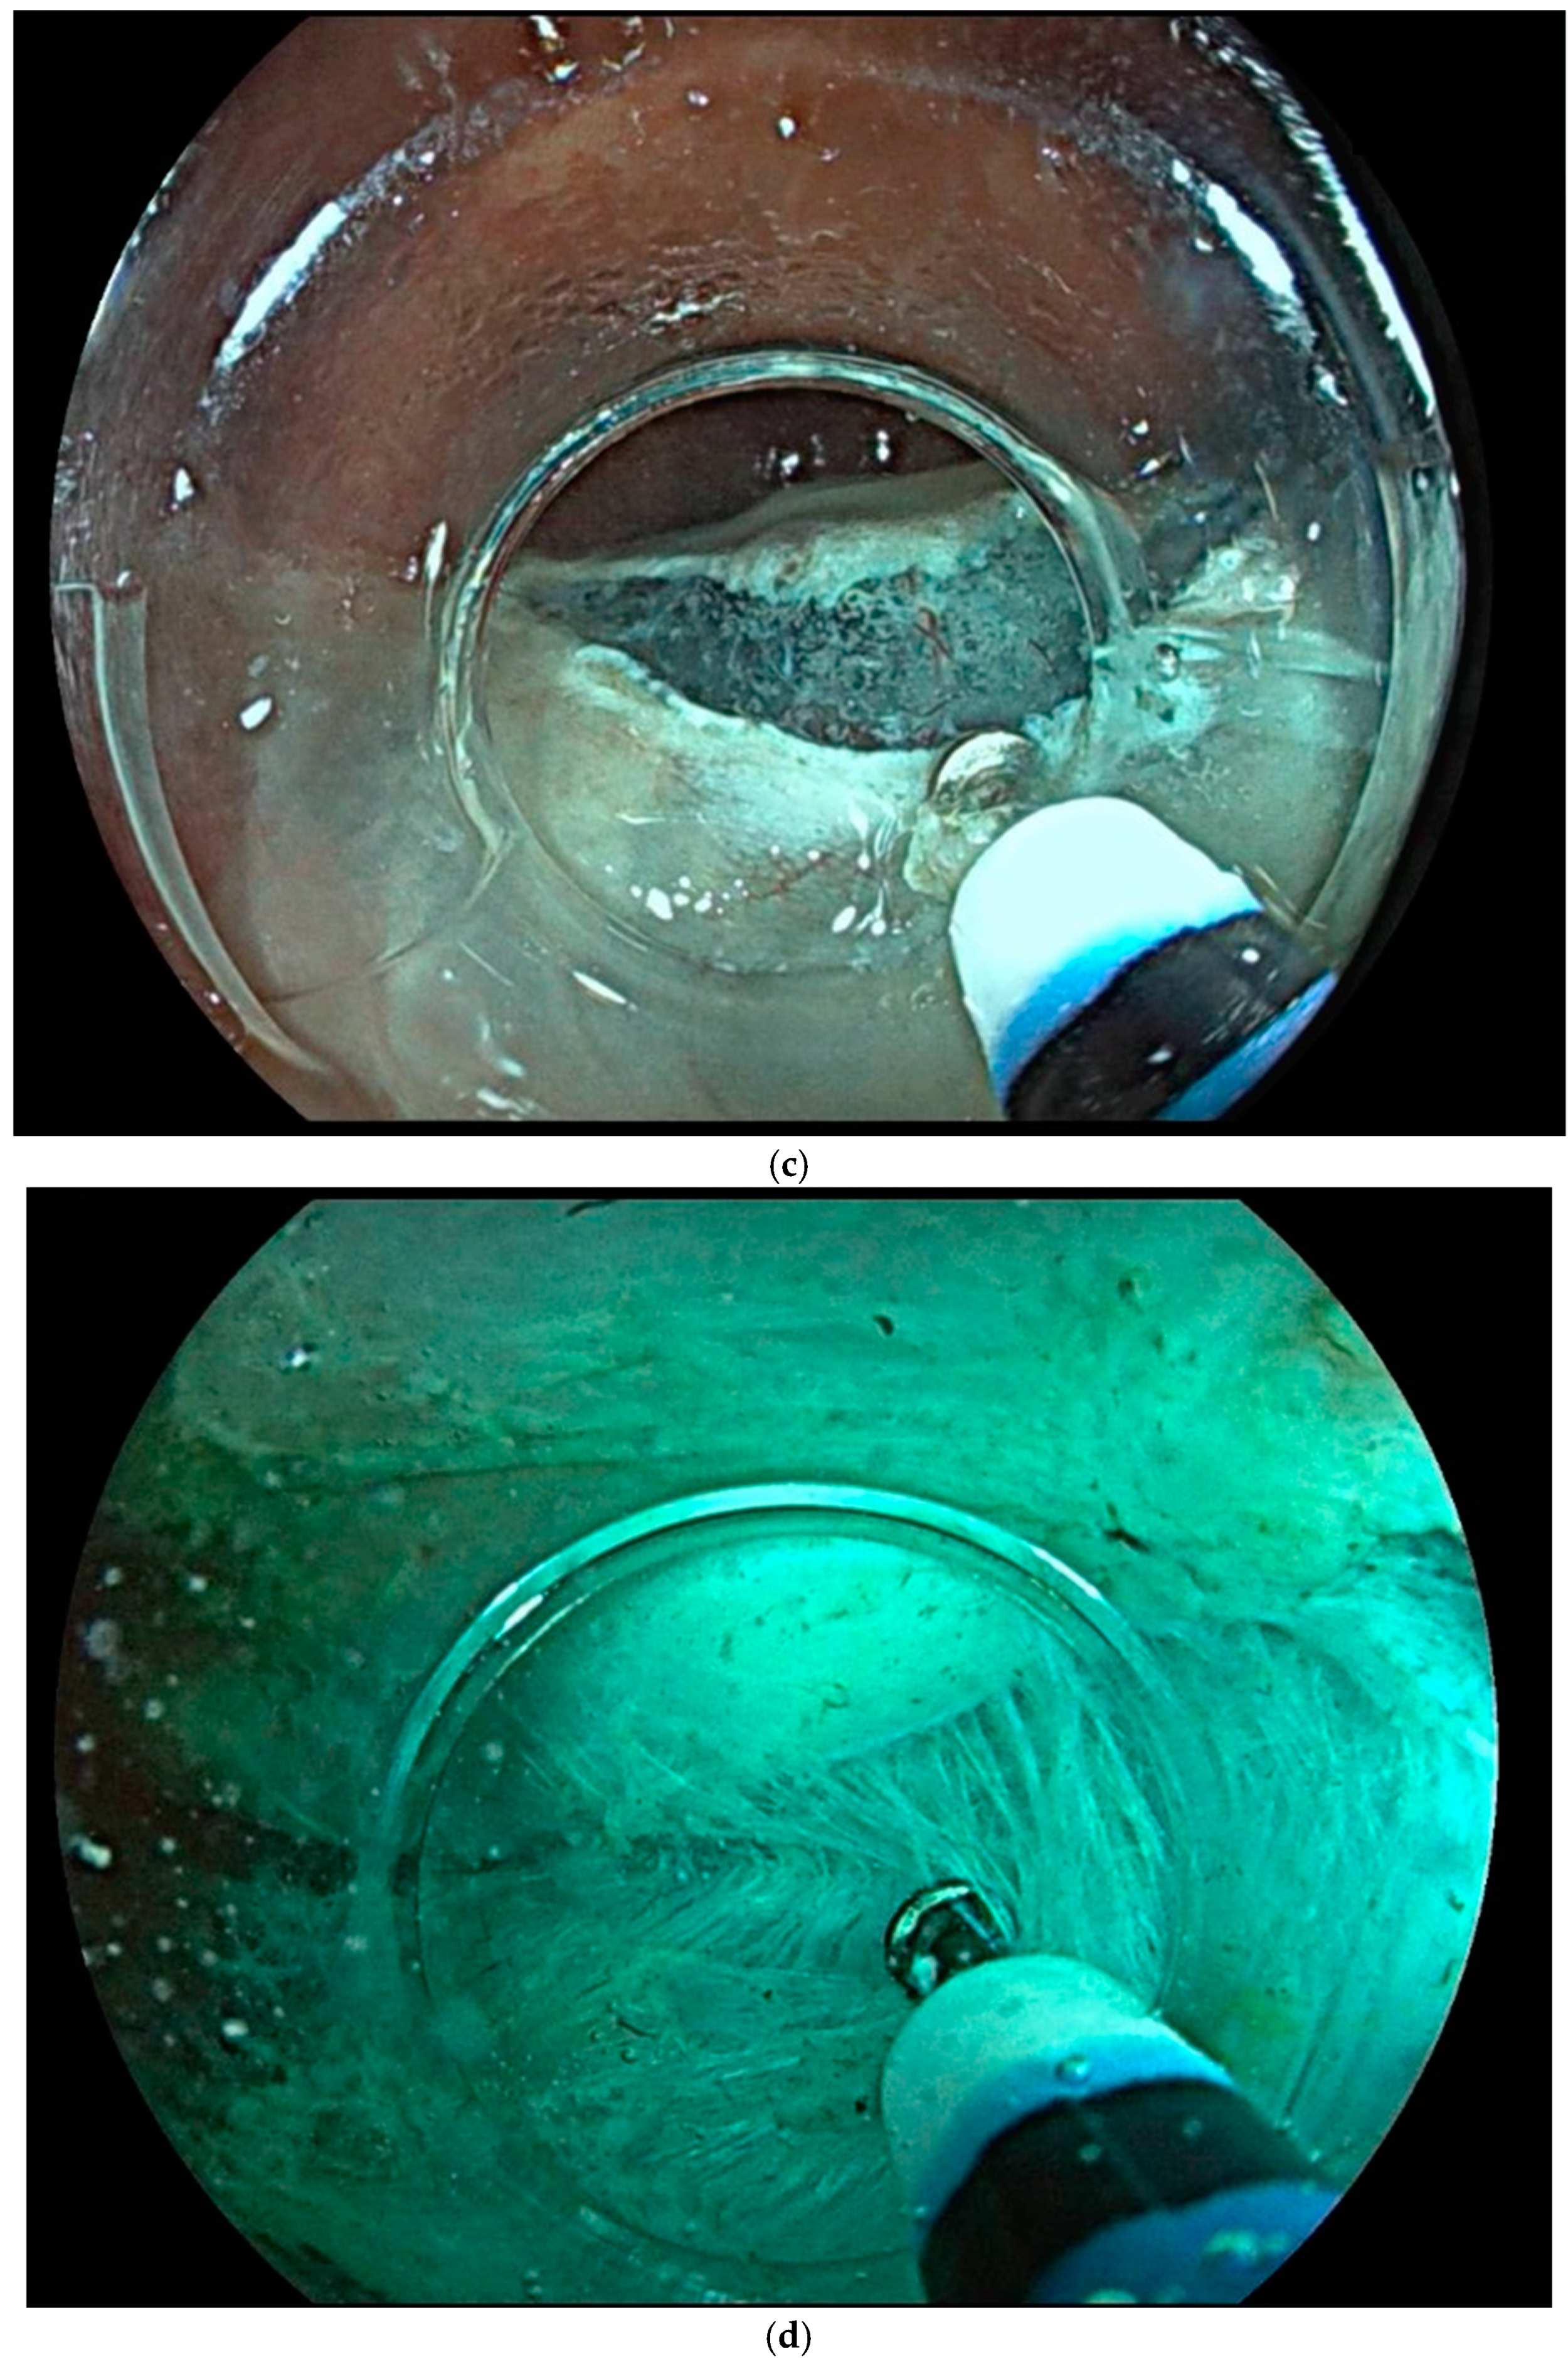

8. Endoscopic Resection Techniques

| Endoscopic mucosal resection (EMR) involves injection of a solution into the submucosal space in order to separate the mucosal lesion from the underlying muscularis propria. The lesion can then be resected by snare electrosurgery. The submucosal cushion theoretically reduces the risk of thermal or mechanical injury of the underlying muscularis propria [81]. | ![]() |

| Endoscopic submucosal dissection (ESD) is characterized by three steps: fluid injection into the submucosa in order to swell the lesion from the muscle layer and circumferential cutting of the mucosa surrounding the lesion, followed by dissection of the submucosal connective tissue beneath the lesion (standard technique). The major advantages of this technique in comparison with polypectomy or EMR include control of the resected size and shape, possible en bloc resection even in a large lesion and also resectability of the lesions in case of submucosal fibrosis. Disadvantages include the time-consuming procedure associated with a higher risk of complications (mainly bleeding and perforation) when compared with EMR [83]. | ![]() |